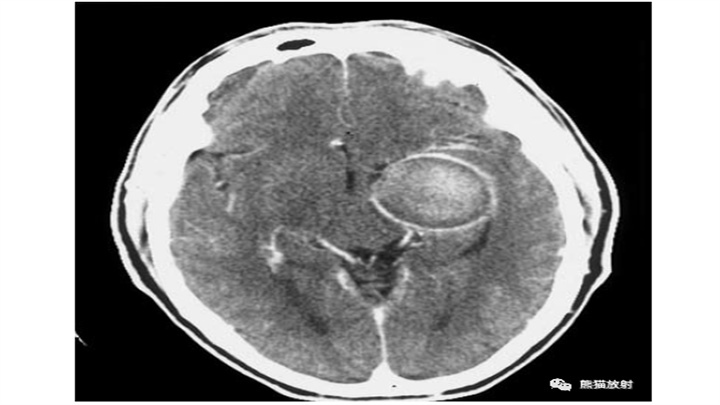

类固醇对外围环的影响。在发作后的第17天,IPH的中心密度降低,大量的局灶性水肿和离散效应。可的松治疗后,外围环不完全且模糊(箭头)。